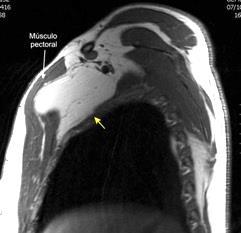

48 MASAS. LIPOMA SUBPECTORAL

Densidad similar al músculo con estriaciones internas de grasa

Hallazgo incidental . Región infraescapular 2% de TC del tórax. Bilateral 60%.

Burt AM et al. Imaging review of lipomatous musculoskeletal lesions. SICOT J2017/ Murphey MD et al. From the archives of the AFIP: benign musculoskeletal lipomatous lesions. Radiographics. 2004

Isointenso con grasa subcutánea